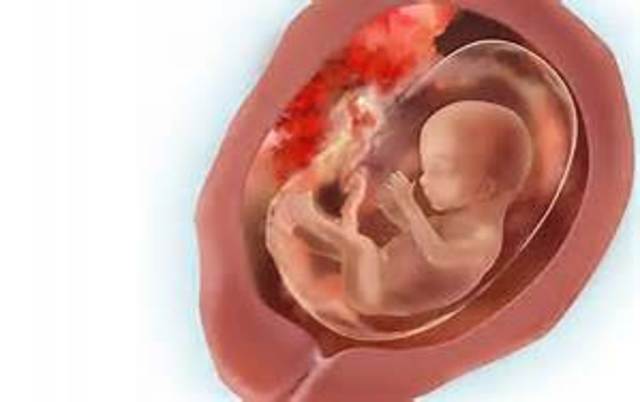

During week nineteen the baby's reproductive organs start to develop and fall in place. Also by this week, the baby is about 6.5 inches.

• Week 20

Week 20

During week twenty, the midpoint of your pregnancy, the baby is about seven inches long and weighs about eleven ounces. From this point onward the baby reacts to sounds outside the womb and can even recognize the voice of its own mother.